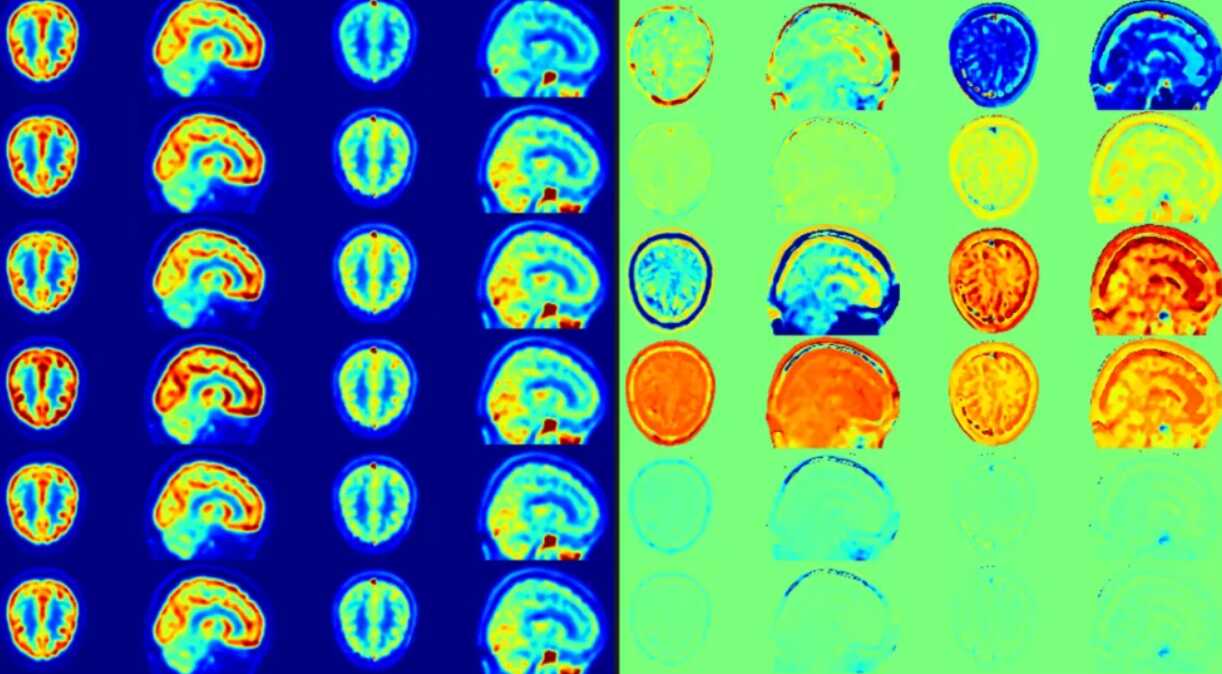

科研进展